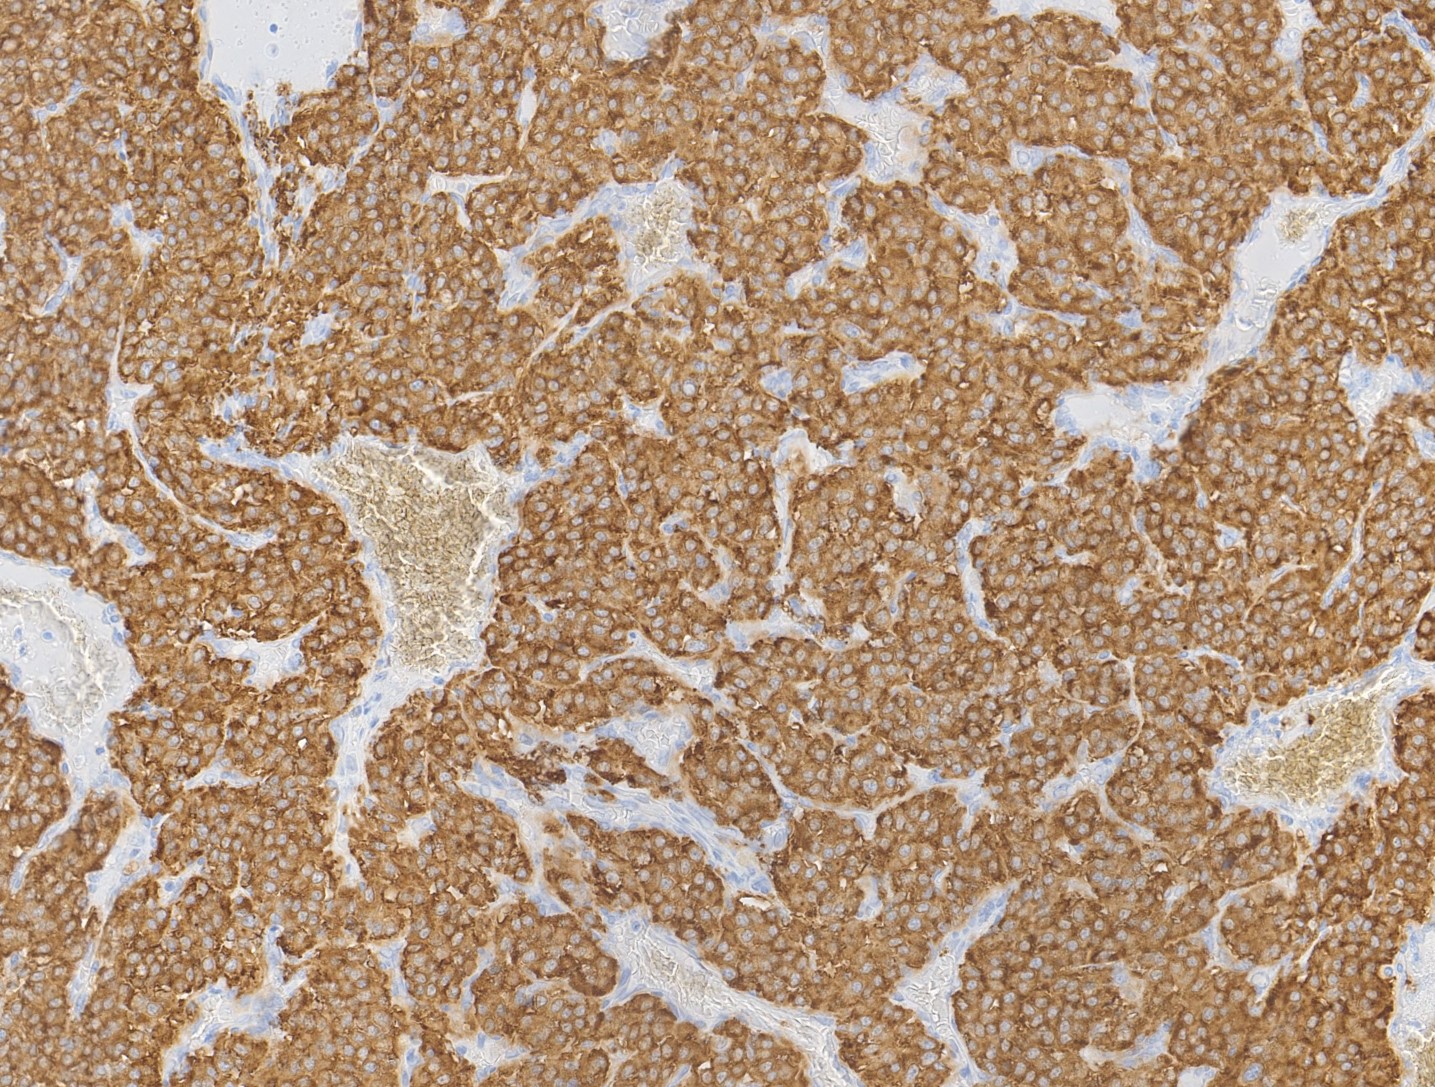

Special stains:

Carotid body paragangliomas are slow growing, well circumscribed tumors with a reddish-brown, firm cut surface. Hemorrhage and cystic degeneration may be seen. On microscopy, nests of oncocytic cells ("zellballen"), often with prominent intranuclear cytoplasmic pseudoinclusions, are surrounded by a fibrovascular network including small spindled sustentacular cells. As demonstrated by this case, an organoid growth pattern is most common in head and neck paragangliomas, but trabecular and solid growth, spindled areas, pigmentation, stromal sclerosis and even amyloid deposition have been described (Head Neck Pathol 2015;9:300). The sustentacular cells stain with S100 and the tumor cells with neuroendocrine markers (synaptophysin, chromogranin, CD56). A reticulin stain will highlight the fibrovascular network. Management is surgical resection (Arch Pathol Lab Med 2014;138:182).

Special stains:

Carotid body paragangliomas are slow growing, well circumscribed tumors with a reddish-brown, firm cut surface. Hemorrhage and cystic degeneration may be seen. On microscopy, nests of oncocytic cells ("zellballen"), often with prominent intranuclear cytoplasmic pseudoinclusions, are surrounded by a fibrovascular network including small spindled sustentacular cells. As demonstrated by this case, an organoid growth pattern is most common in head and neck paragangliomas, but trabecular and solid growth, spindled areas, pigmentation, stromal sclerosis and even amyloid deposition have been described (Head Neck Pathol 2015;9:300). The sustentacular cells stain with S100 and the tumor cells with neuroendocrine markers (synaptophysin, chromogranin, CD56). A reticulin stain will highlight the fibrovascular network. Management is surgical resection (Arch Pathol Lab Med 2014;138:182).